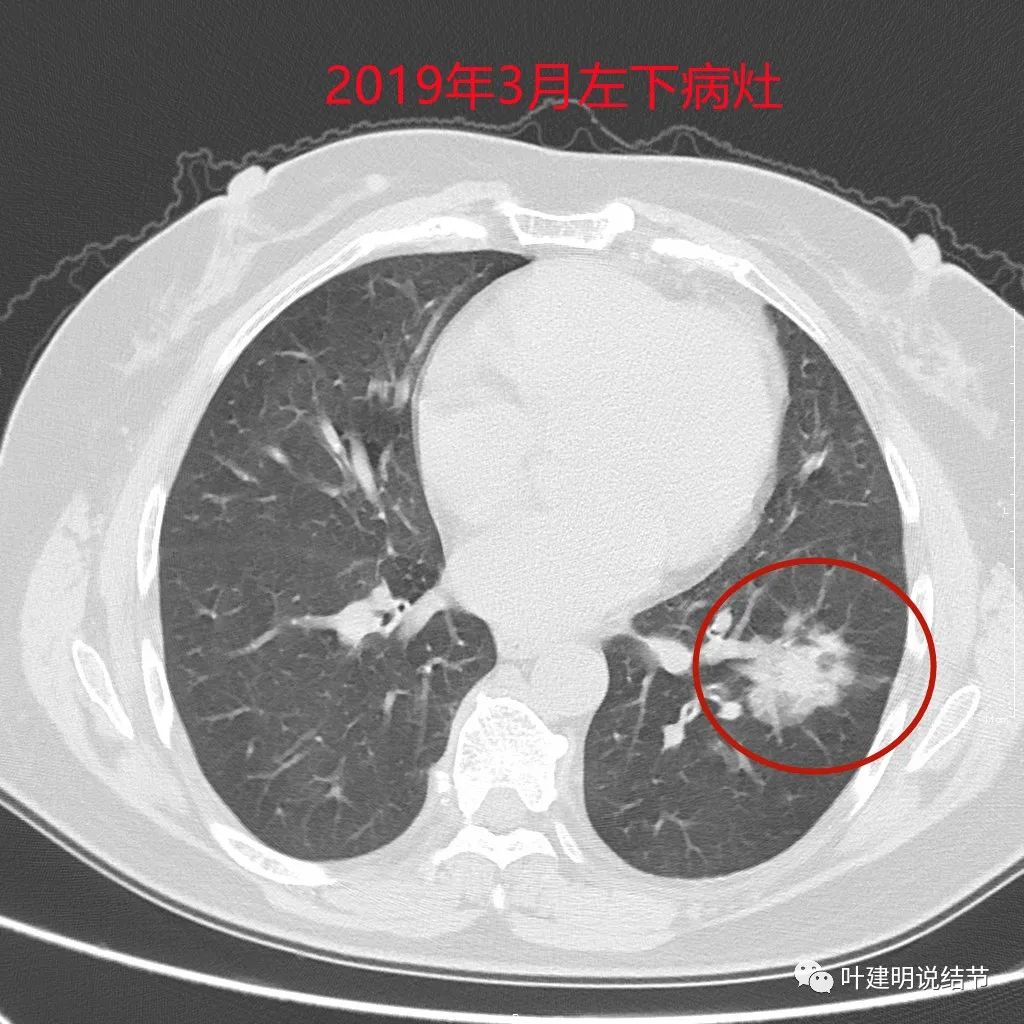

上图是当时左下叶的浸润性腺癌病灶,位置也不好,而且大于3厘米,有实性成分,只能做肺叶切除的。

上图是当时的病理报告。上叶是支气管囊肿伴上皮鳞状化生,伴囊内真菌感染;左下叶是浸润性腺癌,乳头型为主,部分腺泡型,淋巴结是阴性的。但她的肺确实是影响大,下面是术后左肺的样子: